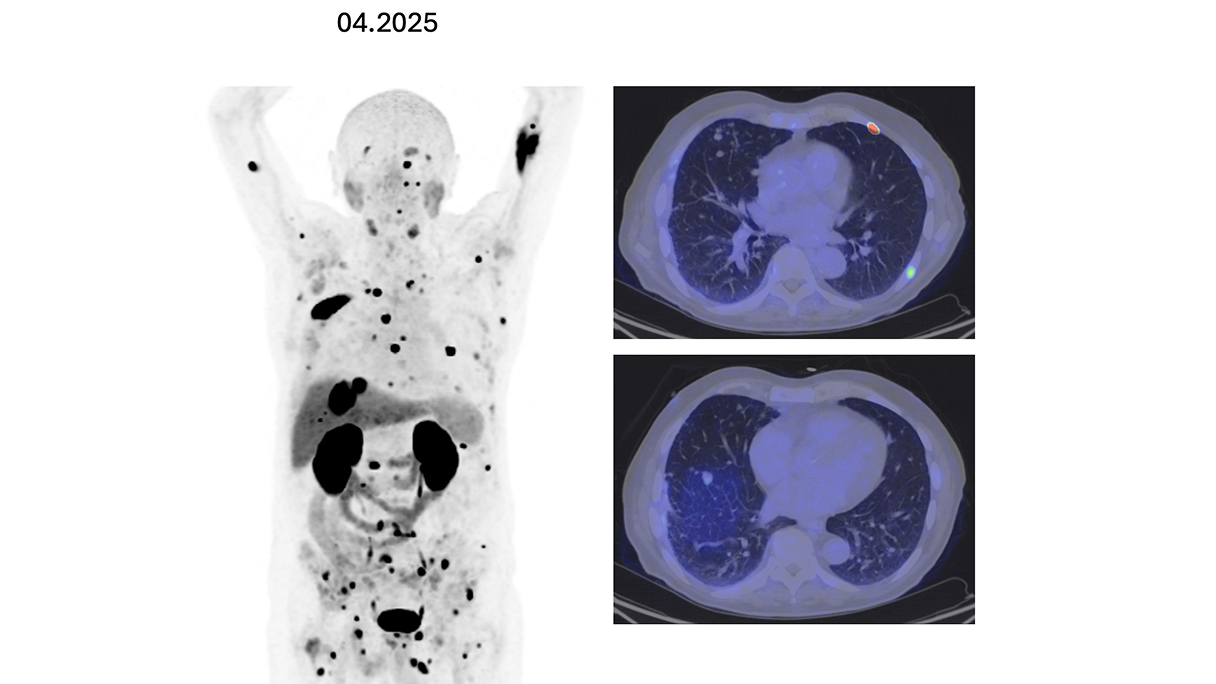

Dentro l'immagine

Fifty shades of grey

Caso condiviso da Marcello De Santis

Casi clinici

Scopri come le tecnologie di imaging più innovative di GE HealthCare hanno giocato un ruolo chiave nella diagnosi di condizioni cardiache complesse.